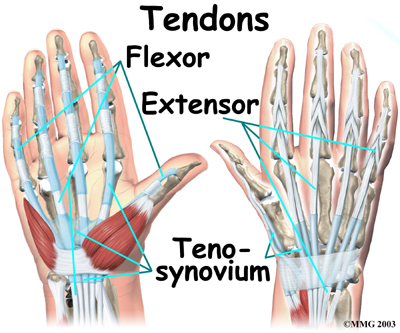

There are several important that cross the wrist.

Tendons connect muscles to bone. The tendons that cross the wrist begin as muscles that start in the forearm. Those that cross the palm side of the wrist are the flexor tendons. They curl the fingers and thumb, and they bend the wrist. The flexor tendons run beneath the transverse carpal ligament (mentioned earlier). This structure lies on the palm side of the wrist. This band of tissue keeps the flexor tendons from bowing outward when you curl your fingers, thumb, or wrist. The tendons that travel over the back of the wrist, the extensor tendons, run through a series of tunnels, called compartments. These compartments are lined with a slick substance called tenosynovium, which prevents friction as the extensor tendons glide inside their compartment.

Tendons connect muscles to bone. The tendons that cross the wrist begin as muscles that start in the forearm. Those that cross the palm side of the wrist are the flexor tendons. They curl the fingers and thumb, and they bend the wrist. The flexor tendons run beneath the transverse carpal ligament (mentioned earlier). This structure lies on the palm side of the wrist. This band of tissue keeps the flexor tendons from bowing outward when you curl your fingers, thumb, or wrist. The tendons that travel over the back of the wrist, the extensor tendons, run through a series of tunnels, called compartments. These compartments are lined with a slick substance called tenosynovium, which prevents friction as the extensor tendons glide inside their compartment.

At the wrist, the end of the ulna bone of the forearm articulates with two carpal bones, the lunate and the triquetrum. Tendons connect muscles to bone. The tendons that cross the wrist begin as muscles that start in the forearm. Those that cross the palm side of the wrist are the flexor tendons. They curl the fingers and thumb, and they bend the wrist. The flexor tendons run beneath the transverse carpal ligament (mentioned earlier). This structure lies on the palm side of the wrist. This band of tissue keeps the flexor tendons from bowing outward when you curl your fingers, thumb, or wrist. The tendons that travel over the back of the wrist, the extensor tendons, run through a series of tunnels, called compartments. These compartments are lined with a slick substance called tenosynovium, which prevents friction as the extensor tendons glide inside their compartment.

Tendons connect muscles to bone. The tendons that cross the wrist begin as muscles that start in the forearm. Those that cross the palm side of the wrist are the flexor tendons. They curl the fingers and thumb, and they bend the wrist. The flexor tendons run beneath the transverse carpal ligament (mentioned earlier). This structure lies on the palm side of the wrist. This band of tissue keeps the flexor tendons from bowing outward when you curl your fingers, thumb, or wrist. The tendons that travel over the back of the wrist, the extensor tendons, run through a series of tunnels, called compartments. These compartments are lined with a slick substance called tenosynovium, which prevents friction as the extensor tendons glide inside their compartment.